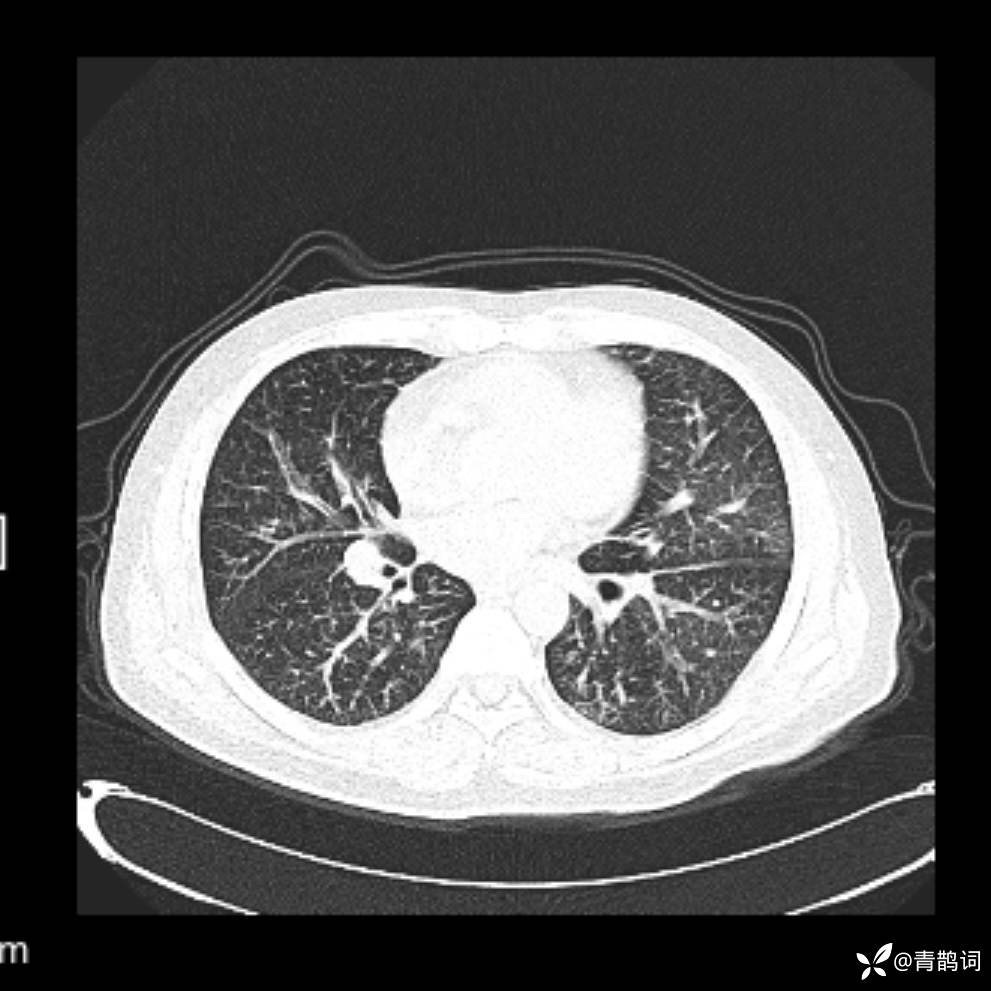

患者年龄:30岁。

患者性别:男。

简要病史:左颜面部肿胀2年,反复咳嗽咳痰,逐渐加重。

辅助检查

结合病史及影像学表现,期待评论区各位老师各抒己见~